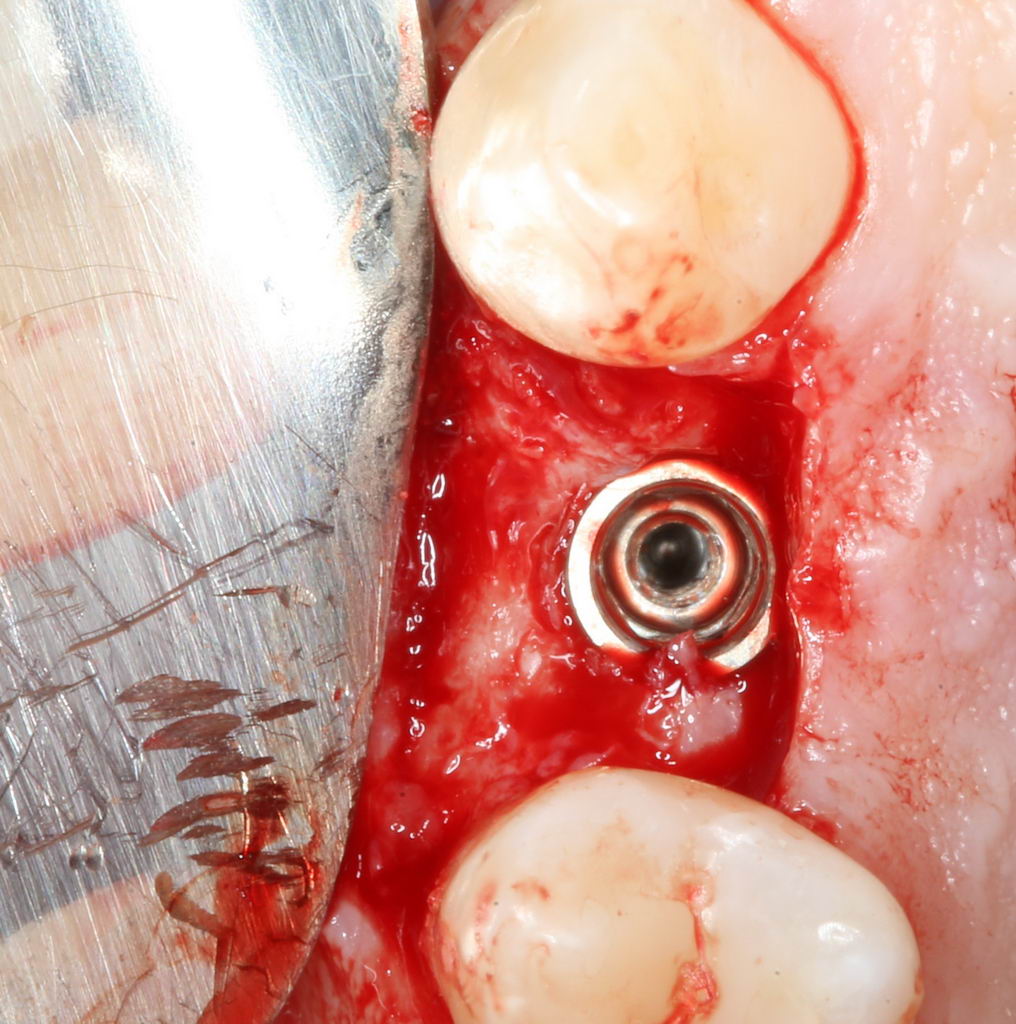

Еще раз проверим положение имплантата:

Учитывая то, что на нём уже установлен временный абатмент TempBase, сделать это очень просто. Фактически, сейчас мы с Вами видим картинку, которую увидит ортопед перед установкой коронки. Это очень удобно.

Больше нам абатмент TempBase не нужен, мы его убираем:

Без абатмента можно оценить позиционирование имплантата по глубине погружения. Напомню, что XiVE — это субгингивальная имплантационная система, поэтому ортопедическая платформа имплантата должна находиться на уровне костной ткани. Что и было выполнено в нашем случае.